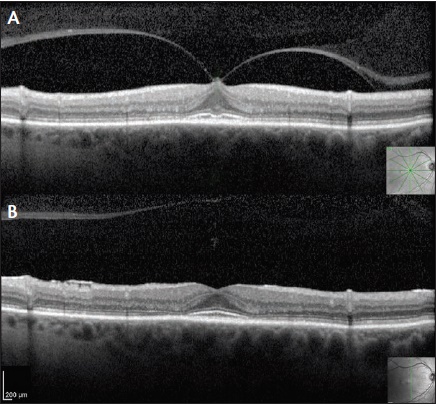

Figure 1. Spectral-domain optical coherence tomography (SD-OCT) scan of a patient with VMT and subsequent spontaneous release. There is a focal area of abnormal adhesion at the fovea with associated traction and distortion of the inner retina. Note how the outer retina is unaffected (A). After 6 months of observation, the VMT resolved with improved foveal contour and normal inner retinal architecture (B).

Over an observation period of approximately 1 year, we found that 21 of 61 (35%) patients experienced VMT resolution and 40 of 61 (65%) did not. Patients with spontaneous release of VMT were significantly more likely to have only inner retinal distortion (P = .01; Figure 1). VMT with solely inner retina disruption is commonly referred to as possessing the column sign, owing to the outer retina being undisturbed in the configuration of two columns (Figure 2). Patients with VMT involving both the inner and outer retina (Figure 3) were unlikely to have spontaneous release of their retinal distortion.